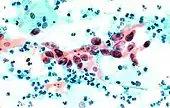

La tinción debería resultar en células que son tan transparentes que incluso las muestras gruesas donde se superponen las células pueden interpretarse.[2] Los núcleos celulares deben ser nítidos, de color azul a negro[12][13] y los patrones de cromatina del núcleo deben estar bien definidos. El citoplasma celular se tiñe de azul verdoso y la queratina se tiñe de naranja.[5][13]

La eosina Y tiñe las células escamosas epiteliales superficiales, los nucléolos, los cilios y los glóbulos rojos.[2] La tinción de Verde Claro SF tiñe el citoplasma de otras células, distintas de las células escamosas superficiales.[2] Las células superficiales son de color naranja a rosa, y las células intermedias son de color verde turquesa a azul.[12]